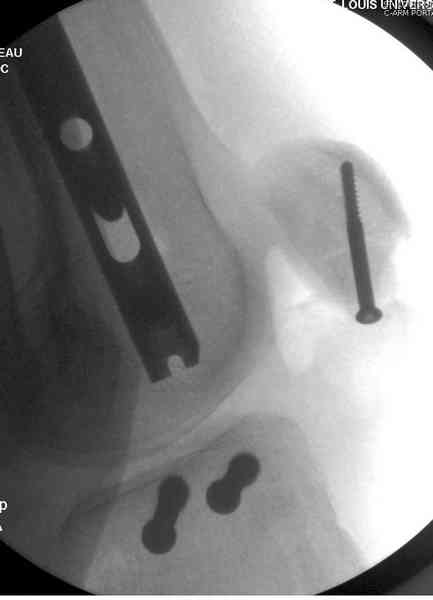

Классическая последовательность открытой редукции состоит из следующих этапов: 1-Восстановление длины и фиксация перелома малоберцовой кости

2 - Реконструкция суставной поверхности большеберцовой кости. 3 - Заполнение

метаэпифизарного дефекта свободным костным трансплантатом. 4 - поддерживающая фиксация с помощью накостных пластин.

На сегодняшний день, стандартом лечения переломов pilon являются протоколы, включающие наложение наружных фиксаторов на 1-3 недели для поддержания длины и восстановления мягких тканей с последующей закрытой или открытой репозицией перелома большеберцовой кости и фиксацией наружным аппаратом в комбинации с минимальной внутренней фиксацией или без неё, ± фиксация малоберцовой кости с помощью платы и шурупов. Голеностопный сустав фиксируется в аппарате 6-12 недель, после чего начинается его разработка, общий срок фиксации в аппарате 12-16 недель, а для переломов проникающих до диафиза – 6 месяцев.